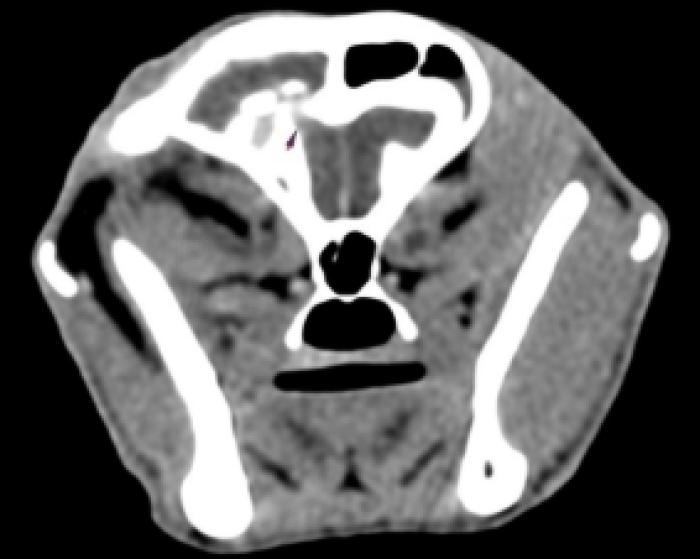

- Resonancia magnética craneal: (día 5) ocupación completa de la cavidad timpánica izquierda (Figura 1A-F) con invasión intracraneal (Figura 1A-C) con edema vasogénico y efecto masa con desplazamiento dorso-medial del lóbulo piriforme, desplazamiento contralateral de la línea media y región talámica izquierda (Figura 1A,D), colapso marcado del ventrículo lateral izquierdo (Figura 1F), y signos de herniación transtentorial e incipiente transforaminal. Se sospecha de infección intracraneal otogénica con formación de absceso en región temporal por extensión de otitis media-interna. Cabe señalar que no se visualizó contenido en las bullas timpánicas.

Revisión clínica y control analítico (día 35): a pesar del tratamiento instaurado, el paciente acude de urgencia debido a que el cuadro progresa con signos neurológicos centrales: marcha en círculos, pressing, anisocoria (pupila izquierda miótica y derecha midriática), respuesta a la amenaza y reflejos pupilares directos e indirectos negativos bilateralmente. El paciente no presenta hipertensión ni alteraciones en el fondo de ojo. Se repite hemograma, con empeoramiento del leucograma y fructosamina, con valor nuevamente más bajo, modificándose la pauta de insulina a 2 UI/12 h (Tabla 2) y se añaden ecografía abdominal (sin alteraciones relevantes) y bioquímica completa con parámetros hepáticos (transaminasas, bilirrubina y ácidos biliares pre-prandiales), lipasa específica felina y tiroxina total en rango fisiológico. Ante la sospecha de infección intracraneal, se añade a la pauta de antibioterapia trimetoprima-sulfametoxazol a dosis de 15 mg/kg/12 h y se realiza tomografía computarizada (TC) de cráneo.

TC: efecto masa compatible con absceso, ocupando senos frontales, con osteomielitis del hueso frontal derecho, miositis y absceso en musculatura temporal derecha en contacto con hueso frontal, afectación intracraneal en área epidural del lóbulo temporal derecho con desviación de línea media de hemisferios (sin afectación de parénquima). Se observa además moderada pérdida de cornetes nasales en cavidad nasal derecha, sin secreciones asociadas y linfadenopatía regional derecha de tipo reactivo (Figura 6A-F). Se drena el contenido del absceso más superficial y se envía al laboratorio externo para su estudio microbiológico (cultivo y antibiograma).